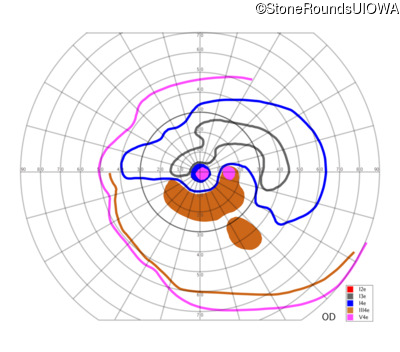

AR Stargardt Disease (IIA)

AR Stargardt Disease (IIA)

| Age at visit: 12 years |

| Age at visit: 13 years |

| Age at visit: 15 years |

| AR Stargardt Disease | ABCA4 | Leu541Pro CTA>CCA, Ala1038Val GCC>GTC | Gln1003Stop CAG>TAG | AR |